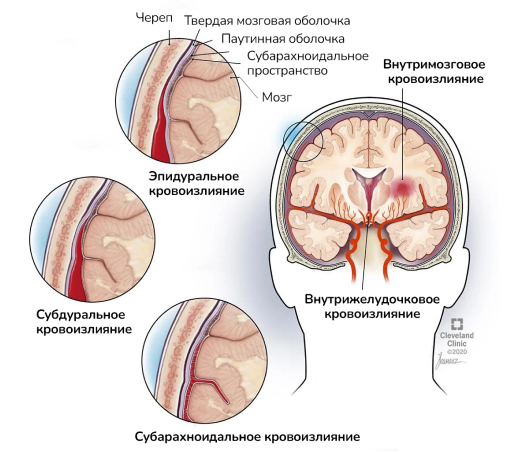

Медицинские аспекты и диагностика субдуральной гигромы мозга